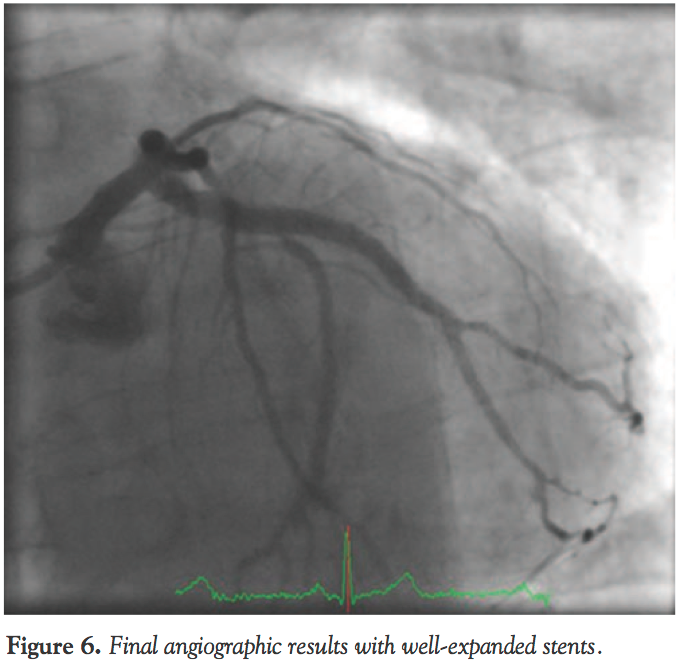

The 1.4 mm laser catheter was used again at 40/40 with concomitant contrast injection while lasing, and this resulted in the catheter passing (Figure 4). Subsequent dilatation was performed with a 3.5 mm non-compliant balloon, which expanded the old under-expanded stent (Figure 5). Subsequently, two DESs (Xience 3.0 x 18 mm and 4.0 x 18 mm) were inserted and postdilated with a 4.0 non-compliant balloon with excellent final results (Figure 6). The patient tolerated the procedure well with no complications and he was monitored on the ward and allowed home in a stable condition on secondary prevention measures and dual antiplatelet therapy.